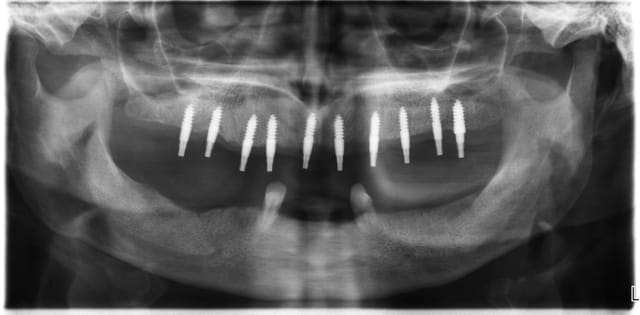

3ème photo: radio d´un patient âgé de 73 ans qui souhaitait avoir des dents fixées.Comme on l´observe il n a plus de place après les foramines mentales.Nous avons donc utilisé juste l´os interforaminal. Nous avons suivi le concept du prof. Nentwig qui consiste à pouvoir ajouter 2 dents dans chaque quadrant dans la mandibule.

Je sais bien que 8 implants auraient suffit cependant 10 ont été posés.Nous voulions remplacer chaque racine avec un implant.

Le patient n a jamais eu de problèmes ( juste avec une hygiène buccale normale, brosse à dents).

Ça me fascine de te voir poser 10 implants en flapless à la mandibule sans guide ici, et réussir. On pourra discuter la méthode, mais pas la main du chirurgien. Bravo.

+1, même si je trouve qu'il y a un peu trop de titane...

çà n'était pas pour le coût...mais pour le respect des distances entre chacun des implants...amha en bas 8 auraient suffit...

Tu as raison 8 auraient suffit normalement, mais l expérience nous a montré que les règles traditinelles ne sont pas valables pour les implants posés en minimal invasiv. En préservant le perioste on conserve une bonne nutrition peri implantaire et donc on peut faire des implants rapprochés sans danger ....